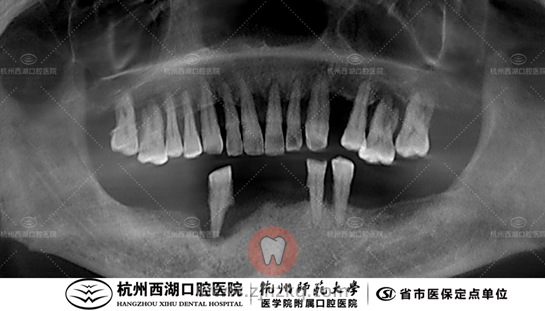

术后CBCT照如下

术后的杨叔叔非常开心,也按时来复查,还把夫人的种牙也安排上了,生活甜甜蜜蜜,让人羡慕。想要种植牙可以来杭州西湖口腔医院,希望大家都能够有好牙好口福!